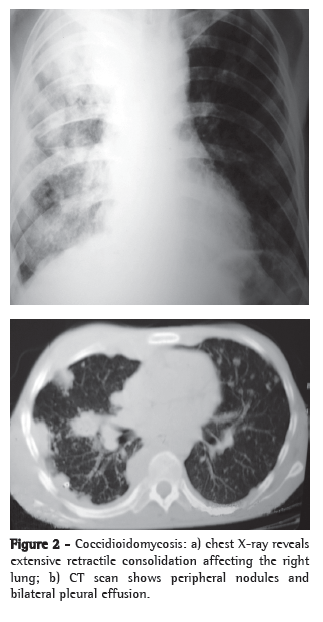

Other testsNonspecific tests that are useful for the evaluation of patients include X-rays and CT scans of the affected site, principally of the chest, and can greatly aid in the diagnosis (Figures 2 and 3). The most common findings on chest X-rays are multiple lung nodules of peripheral distribution, associated with parenchymal consolidation. CT scans of the chest reveal peripheral lung nodules that are predominantly cavitated.(29,39)